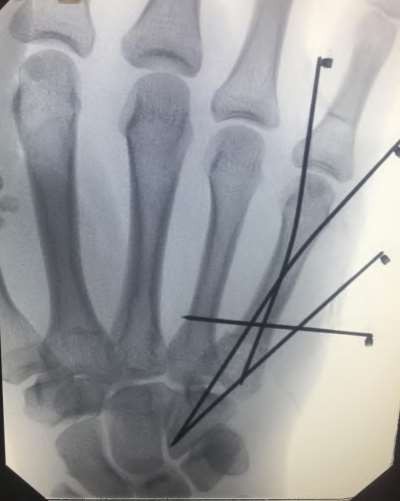

A 35-year-old woman reports wrist pain after a fall onto an outstretched hand. On exam, she has focal tenderness over the wrist snuffbox. A radiograph and CT image are shown in Figures A and B. What is the proper treatment of her injury?